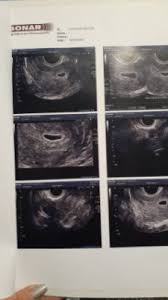

6 Semanas So O Saco Gestacional E A Visicula Sera Que E Gravidez Babycenter

Gestacao A Primeira Ecografia Maternidade Simples